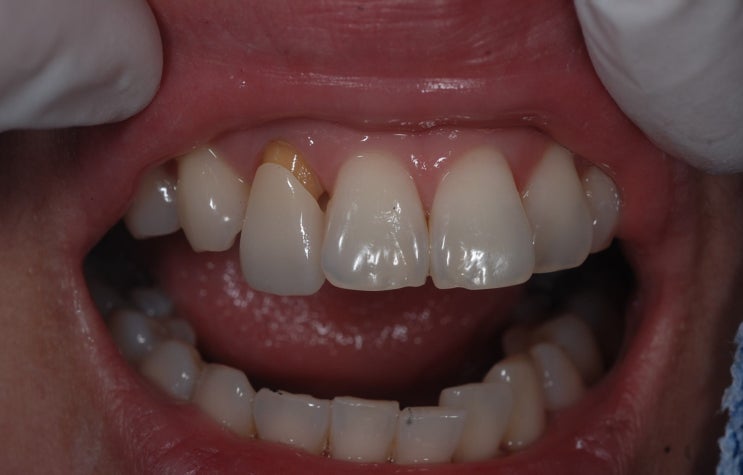

[일원동 치과] 전치부 파절로 인한 임플란트 보철

안녕하세요 수서역 치과 일원동 치과 수서신혼희망타운 치과 수서서울삼성치과 원장 이재현입니다 오늘은 ...